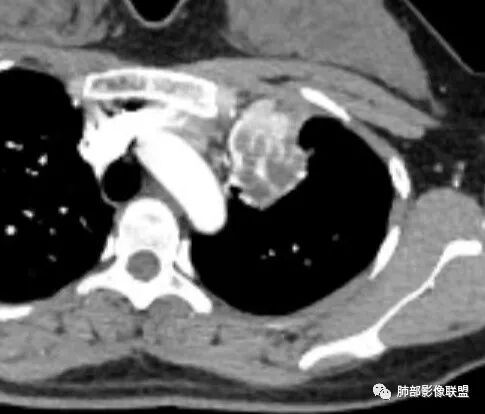

腔内,不是黏液,我觉得是长东西了

黏表一例 供参考:

拿出来只是给大家提个醒,不是说没强化就不是癌

其实黏表和结核的鉴别,不是局部开口处是否强化,而是结核的粘液栓没有强化,而黏表的粘液栓中含有肿瘤细胞生长,会有不均匀强化。晨读那些低密度区都看不到强化。就不太符合黏表了。